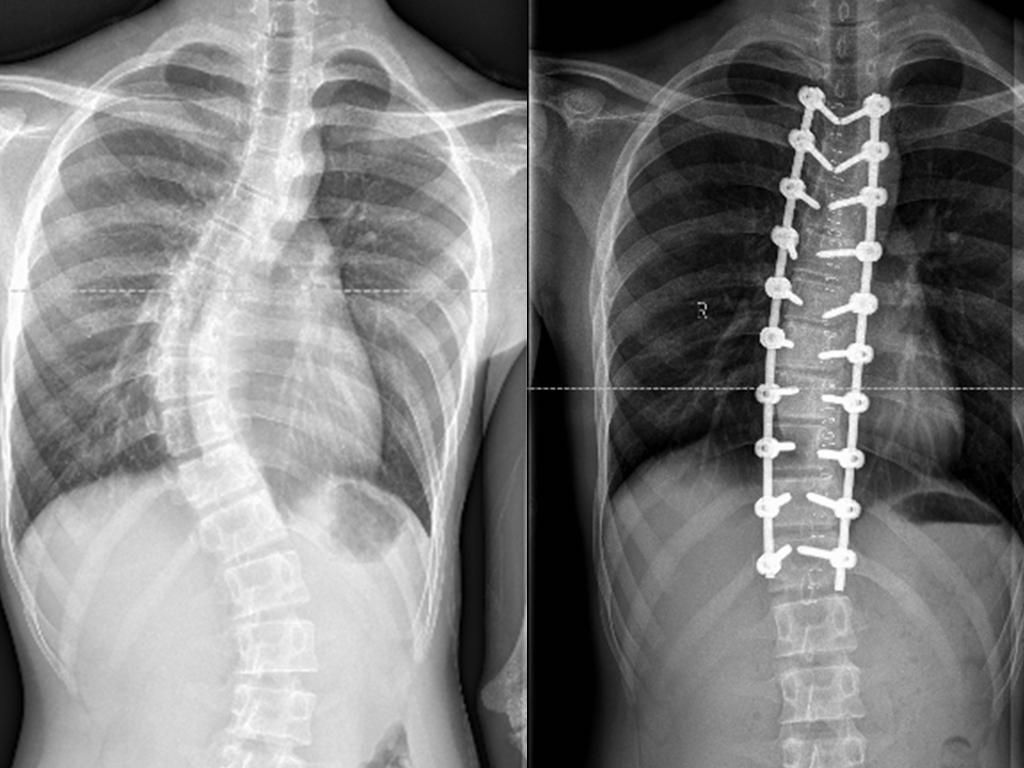

在父母的带领下小罗来到简阳市人民医院脊柱门诊,副主任医师贾叙锋通过相关检查发现,小罗脊柱侧弯度数达到45°,属于青少年特发性脊柱侧弯,符合手术指征。脊柱侧弯矫形手术关键在于精确置钉、截骨、矫形,小罗脊柱已旋转、变形、变异,置钉稍有偏差或失败,轻者可能出现脊髓、神经损伤,重者可致患者瘫痪,所以脊柱侧弯矫形手术风险大、难度高。在得知简阳市人民医院与四川大学华西医院骨科建立了专科联盟,医院骨科是成都市重点专科时,让小罗的家人对手术充满了信心。

科室主任戢勇指导,贾叙锋医生与团队反复研究影像学资料中小罗每个椎体椎弓根的直径、角度,一遍又一遍梳理手术中可能预见的特殊情况及处理应对方案,重复预演整个脊柱矫形过程,拟定了个性化的诊疗手术方案。4月27日,经过团队5个小时的努力,采用旋棒、凹侧撑开、凸侧加压等技术实施矫形并固定,成功为小罗的脊柱侧弯实施了矫形手术。术后小罗侧弯脊柱得以矫正,打直了背的小罗重新充满笑容,身高比过去还增高了5厘米,